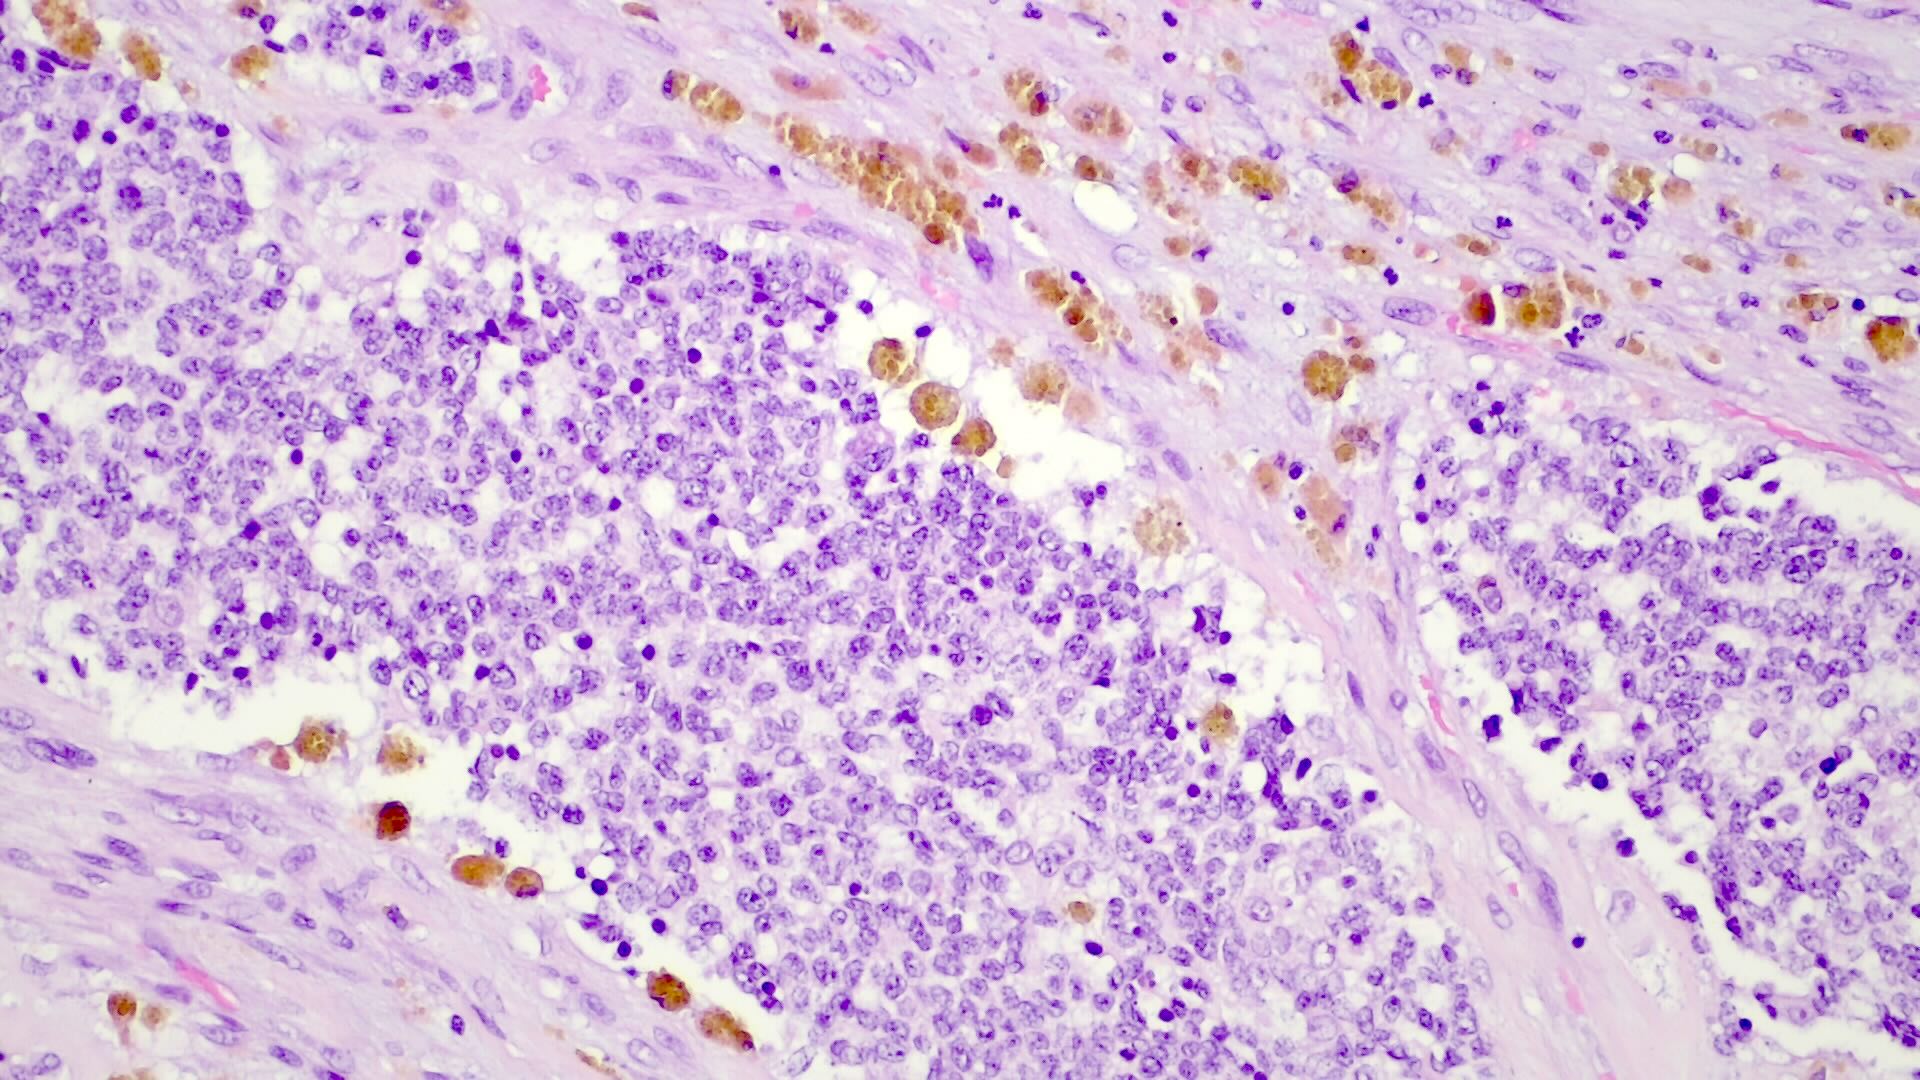

- Epithelial hepatoblastoma may exhibit several patterns (alone or in combination): fetal, embryonal, small cell undifferentiated (SCUD), cholangioblastic and macrotrabecular (J Gastrointest Oncol 2018;9:326)

- Fetal pattern (Pediatr Dev Pathol 2020;23:79)

- Thin trabeculae or nests of small to medium sized cells resembling hepatocytes of the developing fetal liver

- Clear or finely granular cytoplasm with variable amount of glycogen and lipids

- Small round nucleus with indistinct nucleolus

- Foci of extramedullary hematopoiesis are usually present

- Typically has low mitotic activity, referred to as well differentiated hepatoblastoma

- A subset has increased mitotic activity, with decreased cytoplasmatic glycogen and pleomorphic nuclei, referred to as mitotically active hepatoblastoma

Microscopic (histologic) images

Positive stains

- Frequent beta catenin and glutamine synthetase in the epithelial fetal (except the well differentiated and low mitotic subtype) and mesenchymal patterns (Pediatr Dev Pathol 2020;23:79, Biosci Rep 2019;39:BSR20192466)

- AFP in the less differentiated epithelial components

- HepPar1 in the fetal pattern

- Polyclonal CEA

- Glypican 3 in the fetal and embryonal pattern

- Pancytokeratins have variable expression (J Gastrointest Oncol 2018;9:326)